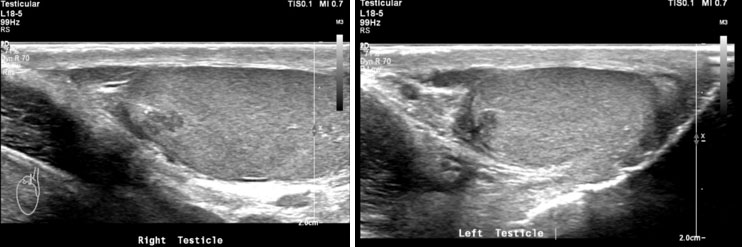

Adrenal rests were noted in both testes; the scrotal ultrasound and MRI showed bilateral eccentric lobulated lesions adjacent to the mediastinum in the testes. No calcification or vascularity was seen in the testicular lesions (Figure 2A, Figure 2B and Figure 3).

Figure 2: Testicular adrenal rests on scrotal ultrasound imaging. (A) Longitudinal ultrasound image of the right testis. (B) Longitudinal ultrasound image of the left testis.

The hallmark of the SV-CAH is virilization in females and precocious puberty in males along with enhanced somatic growth; all due to androgen hypersecretion. The index patient presented with features of peripheral precocious puberty, secondary sexual characteristics, and advanced bone age with no clinical and biochemical features of SW. The revelation of high testosterone level with low FSH and LH associated with pre-pubertal testes size are indicative of peripheral PP in our case [9]. Congenital adrenal hyperplasia is associated with adrenal abnormalities, namely, adrenal hyperplasia, myelolipoma, benign adenoma, and rarely pheochromocytoma [10]. In patients with CAH, myelolipoma is common in those who were diagnosed late or poorly controlled. Although, no adrenal abnormalities were noted in our patient, follow-up imaging of patients with CAH is important especially in those who present with abdominal pain [11]. Male patients may have ectopic adrenal tissue which may be found anywhere along the gonadal descent pathway [10]. The reported prevalence of testicular adrenal rests in patients with CAH is 24% [12]. Classically, the ectopic adrenal tissue in males may be found in the testes. Likewise, testicular adrenal rests were noted in both testes of the index case.